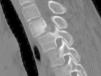

El osteoma osteoide es un tumor óseo benigno de tipo osteoblástico, que representa el 11% de los tumores óseos benignos. Su localización más frecuente es la diáfisis de huesos largos (fémur y tibia), aunque puede afectar otras localizaciones como la columna vertebral. Afecta con más frecuencia a los varones y en edades comprendidas entre los 7-25 años. Clínicamente se caracteriza por dolor continuo de predominio nocturno que suele remitir con AAS. Debe hacerse el diagnóstico diferencial con el osteoblastoma, metástasis y osteomielitis entre otros. El diagnóstico se realiza mediante pruebas de imagen TC (de elección), RNM o gammagrafía. El tratamiento de elección es la resección quirúrgica, aunque en ocasiones se puede realizar la electrocoagulación percutánea con radiofrecuencia.

Osteoid osteoma is an osteoblastic type of benign bone tumor that represents 11% of benign bone neoplasms. It is most frequently found in the diaphysis of the long bones (the femur and tibia), although other areas can be affected, such as the spine. It is most frequently found in male patients aged between 7 and 25 years. This entity is clinically characterized by continuous pain, mainly at night, which can be lessened by the use of acetylsalicylic acid. A differential diagnosis should be made with osteoblastoma, metastasis and osteomyelitis, among other entities. The diagnostic test of choice is computed tomography, while magnetic resonance imaging and scintigraphy are also useful. The treatment of choice is surgical resection, although percutaneous electrocoagulation with radio frequency can sometimes be performed.